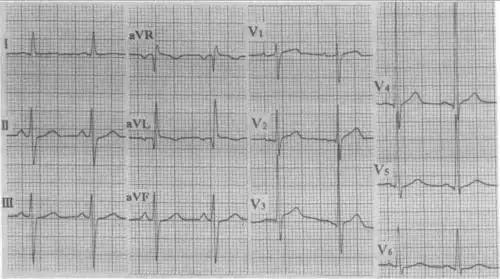

患者男,54岁,图为其常规体检心电图结论:窦性心律左前分支传导阻滞

【定义】 发生于左前分支上的传导延缓或传导中断,称为左前分支阻滞